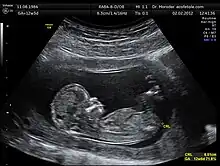

Crown-rump length (CRL) is the measurement of the length of human embryos and fetuses from the top of the head (crown) to the bottom of the buttocks (rump). It is typically determined from ultrasound imagery and can be used to estimate gestational age.

The embryo and fetus float in the amniotic fluid inside the uterus of the mother usually in a curved posture resembling the letter C. The measurement can actually vary slightly if the fetus is temporarily stretching (straightening) its body. The measurement needs to be in the natural state with an unstretched body which is actually C shaped. The measurement of CRL is useful in determining the gestational age (menstrual age starting from the first day of the last menstrual period) and thus the expected date of delivery (EDD). Different human fetuses grow at different rates and thus the gestational age is an approximation. Recent evidence has indicated that CRL growth (and thus the approximation of gestational age) may be influenced by maternal factors such as age, smoking, and folic acid intake. Early in pregnancy gestational age 8 weeks, it is accurate within about +/- 5 days but later in pregnancy due to different growth rates, the accuracy is less. In that situation, other parameters can be used in addition to CRL. The length of the umbilical cord is approximately equal to the CRL throughout pregnancy.